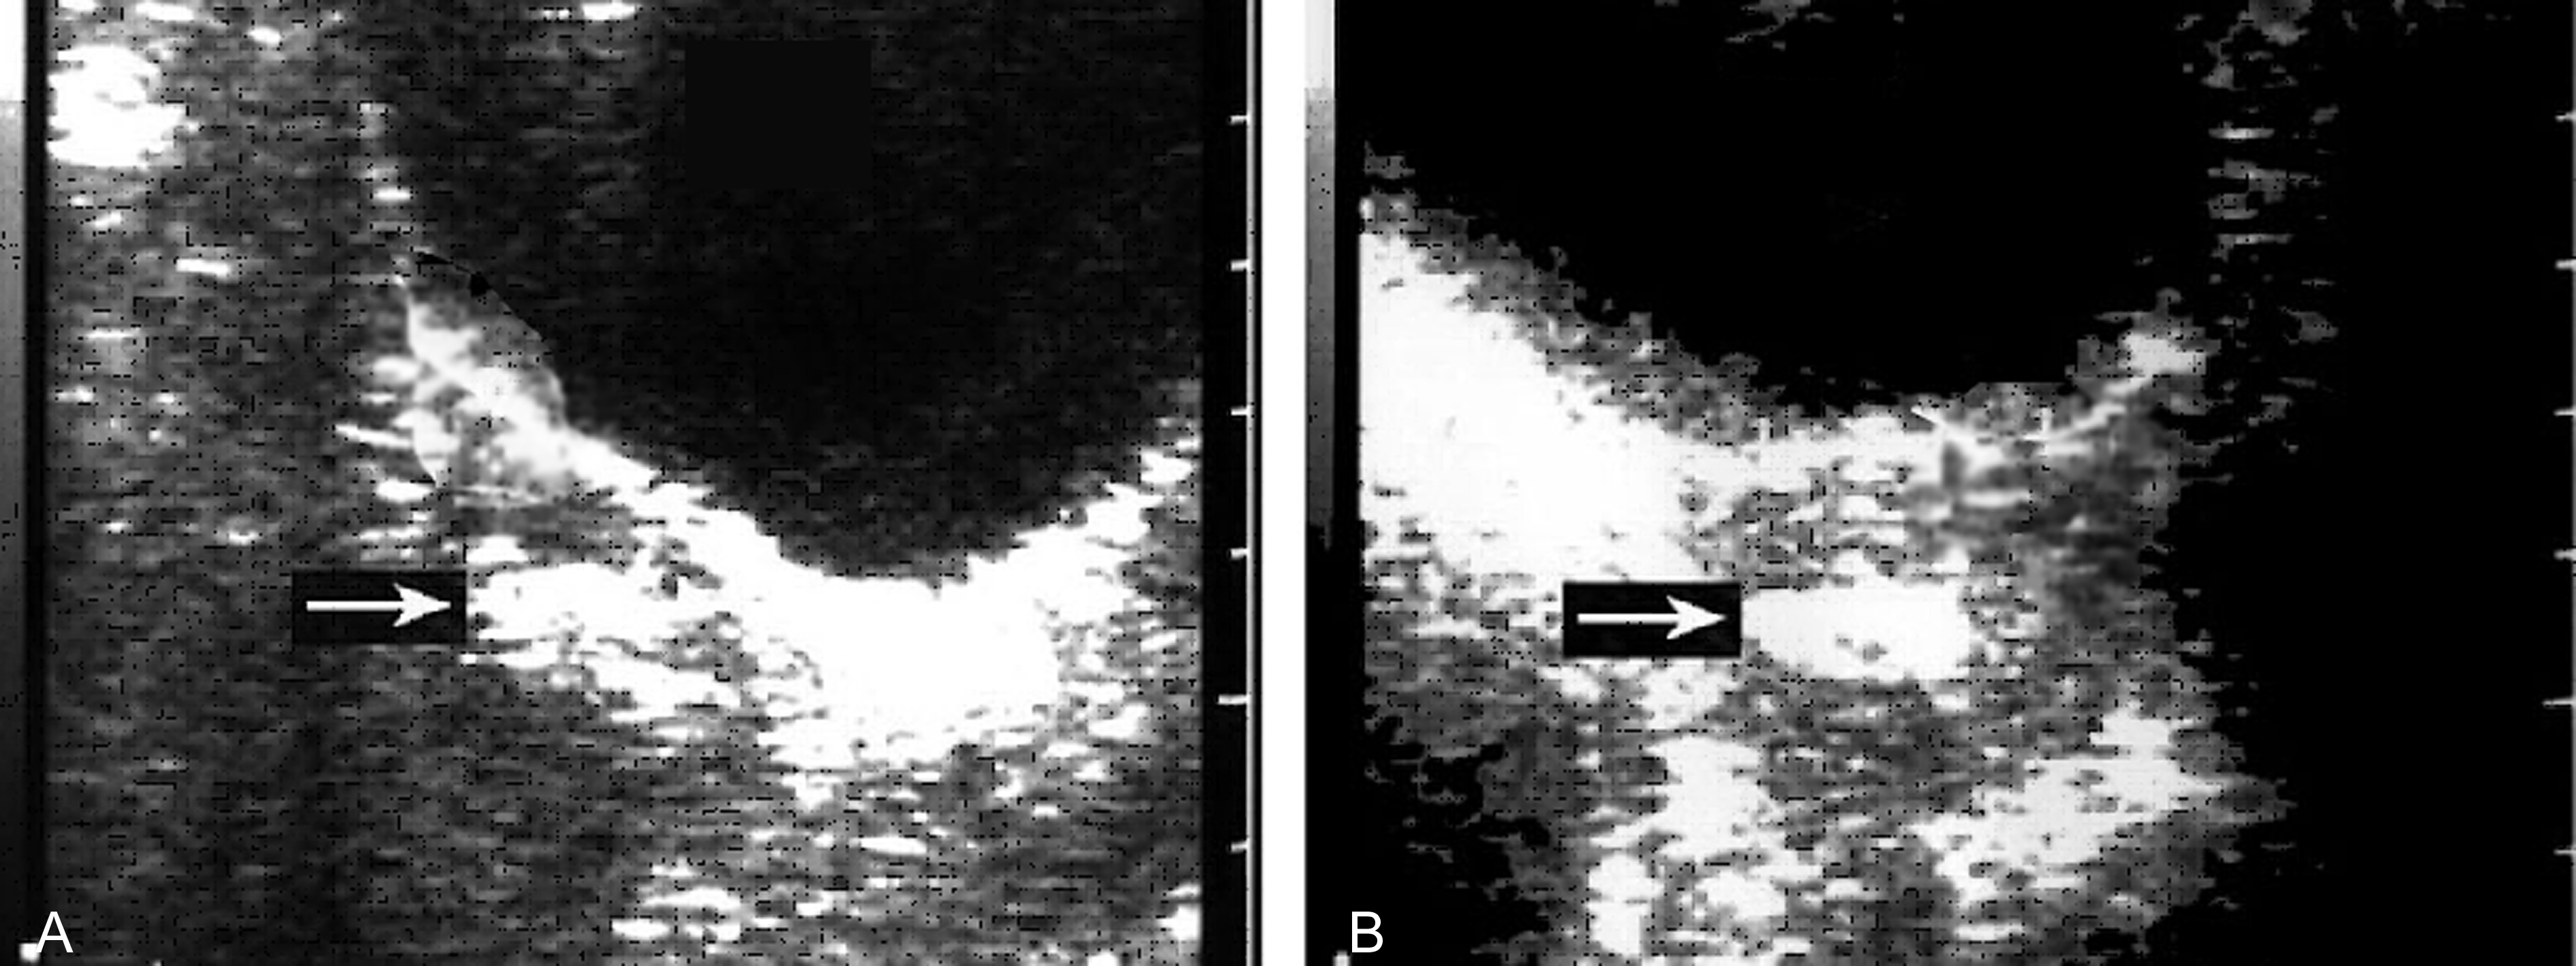

子宫和妊娠囊大小与停经月份相符,回声规则,形态及位置无明显异常变化,妊娠囊内部仍可见存活的胚胎或胎儿,大小与妊娠月份一致。妊娠囊一侧或下方可显示低回声或无回声区,提示有绒毛膜下血肿存在(图1,2),但多数较小,胎盘附着处回声正常;部分声像图可完全无异常发现。

图1绒毛膜下血肿声像图:孕囊(Gs)后方及下方可见不均匀的血块(Ha)回声;C:示意图

图2绒毛膜下血肿声像图:孕囊(GC)下方可见血肿